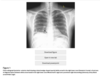

pointing at what, what is this called

thymus: sail sign

what is the finding

what disease is this finding associated with

thymoma (an anterior mediastinal mass)

-Myasthenia Gravis: will present with dysphagia and unable to swallow = bulbar dysfunction

what is the pathiphysiology of myasthenia gravis

autoAb from the thymus against n-Ach R in the neuromuscular junction –> impaired action potential at receptors –> M wkness

will have weakness that is worse throughout the day, often presents with fatiguable chewing or dysphagia